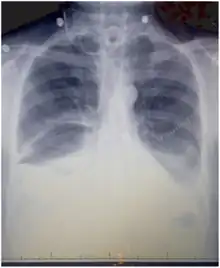

Chest X-rays can detect a chylothorax. It appears as a dense, homogeneous area that obscures the costophrenic and cardiophrenic angles. Ultrasounds can also detect a chylothorax, which appears as an echoic region that is isodense with no septation or loculation. However, neither a normal chest x-ray nor an ultrasound can differentiate a chylothorax from any other type of pleural effusion.[1]

Chest X-ray showing bilateral chylothorax